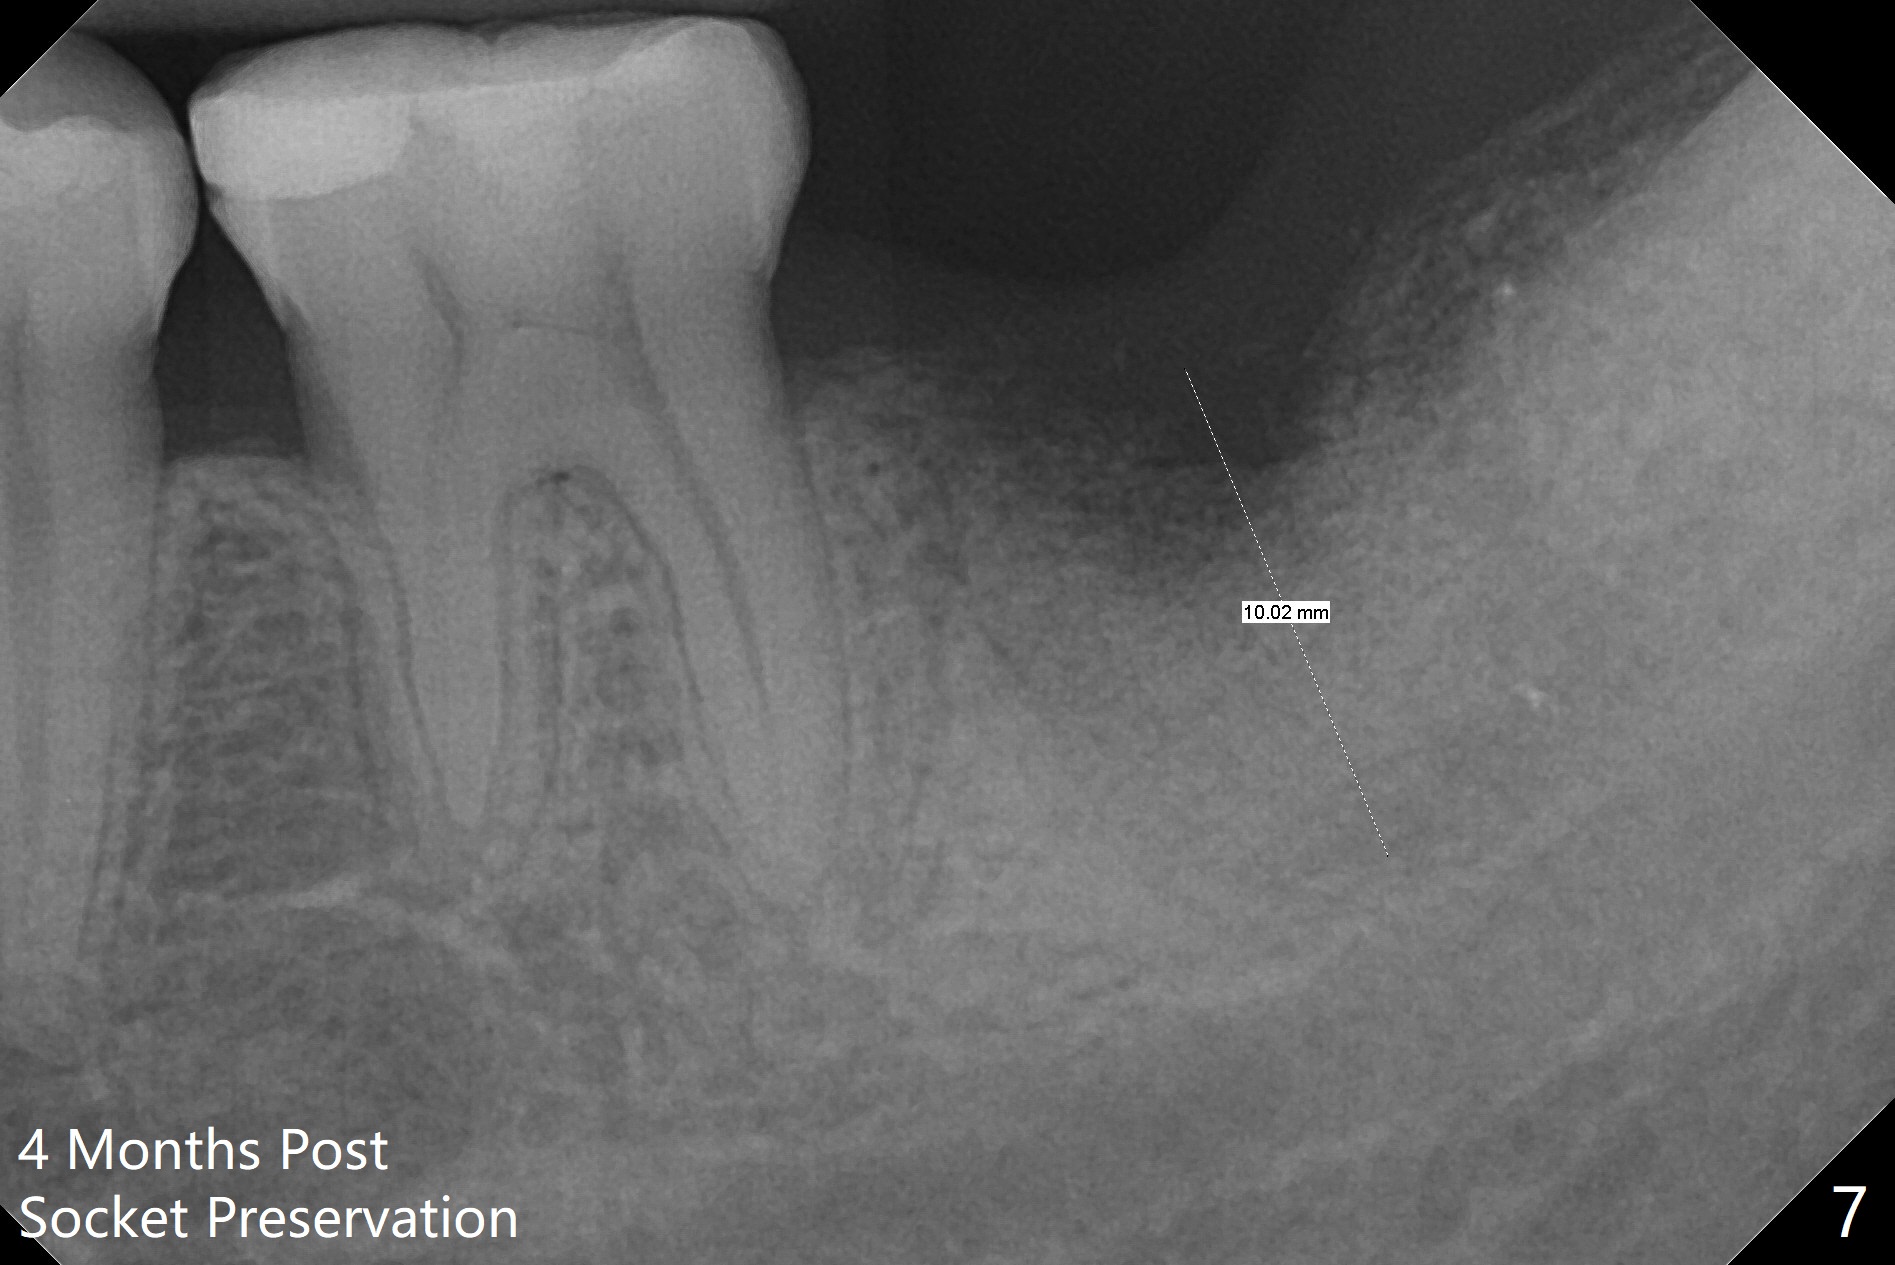

If the patient were not nervous and every step were followed by X-ray, light osteotomy in the bottom of the socket (flattening) may increase primary stability.  A larger implant (9 or 10 mm) is a solution.  The socket heals with disappearance of the fistula 2 weeks postop (Fig.5,6), but the ridge seems to have been reduced in width.  The patient return for follow up 4 months postop; bone graft appears to remain in the socket (Fig.7).  The ridge is apparently reduced further (data not shown).  The patient prefers to have implant placement 1 month later.  Take photos of the ridge buccally when the patient returns.  In fact the patient agrees to have guided surgery.  She postpones the surgery due to sickness for one more month.  Implant placement will occur 6 months post extraction.  The bone density should be higher than earlier.